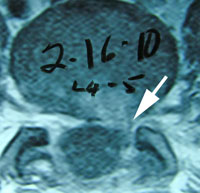

- Case Report: Cervical Spine Post-Surgery

Probably no area of chiropractic spinal manipulation is as challenged as treating the post-surgical patient who is the same, worse, or disenchanted with their surgical outcome. Certainly, the opportunity to treat the patient before surgical intervention is best. When confronted with this post-surgical patient, however, the chiropractic physician proceeds as if with a patient who has not had surgery. i.e. The chiropractor will proceed with the careful history and clinical examination to determine what is causing the pain. That cause may be within the surgical site or adjacent to it. In treating the post-surgical spine, fusion or no fusion is a dictator of care. If there is a fusion, spinal manipulation is given to adjacent levels of the spine to the fused area. If there is no fusion, the doctor carefully proceeds as if no surgery. Some motion may be possible within the spine depending on the surgical procedure performed. (11)